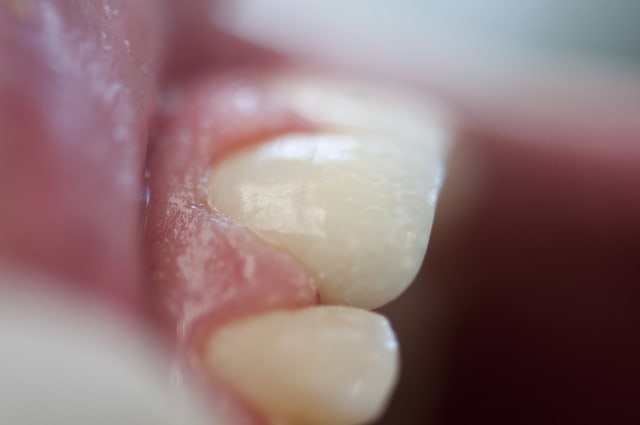

voila quelques traitements,modestes mais je suis encore jeune....